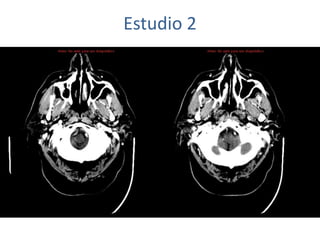

Estudio 2

• Estudio sin y con contraste, con reconstrucciones sagitales y coronales

del estudio con contraste.

Se observa una lesión ocupante de espacio en lóbulo frontal derecho que

presenta un tamaño de 18 x 32 x 22 mm (cc x ap x tr), bilobulada, no del

todo bien delimitada, con realce en anillo irregular, con hipocaptación

central, probablemente por necrosis, y asociada a un extenso edema

vasogénico con efecto masa tanto sobre los surcos de la convexidad

como sobre la cisterna insular, el sistema ventricular y la línea media,

esta última con un desplazamiento de 5 mm a la altura del septo

interventricular.

No se aprecian otras lesiones focales intra o extraaxiales de significación

patológica.

Habría que considerar como primera posibilidad que se tratase de una

lesión metastásica, por bien un tumor primario, aunque no se puede

descartar otras opciones, sin imprescindible correlación con la clínica y

con sus antecedentes.